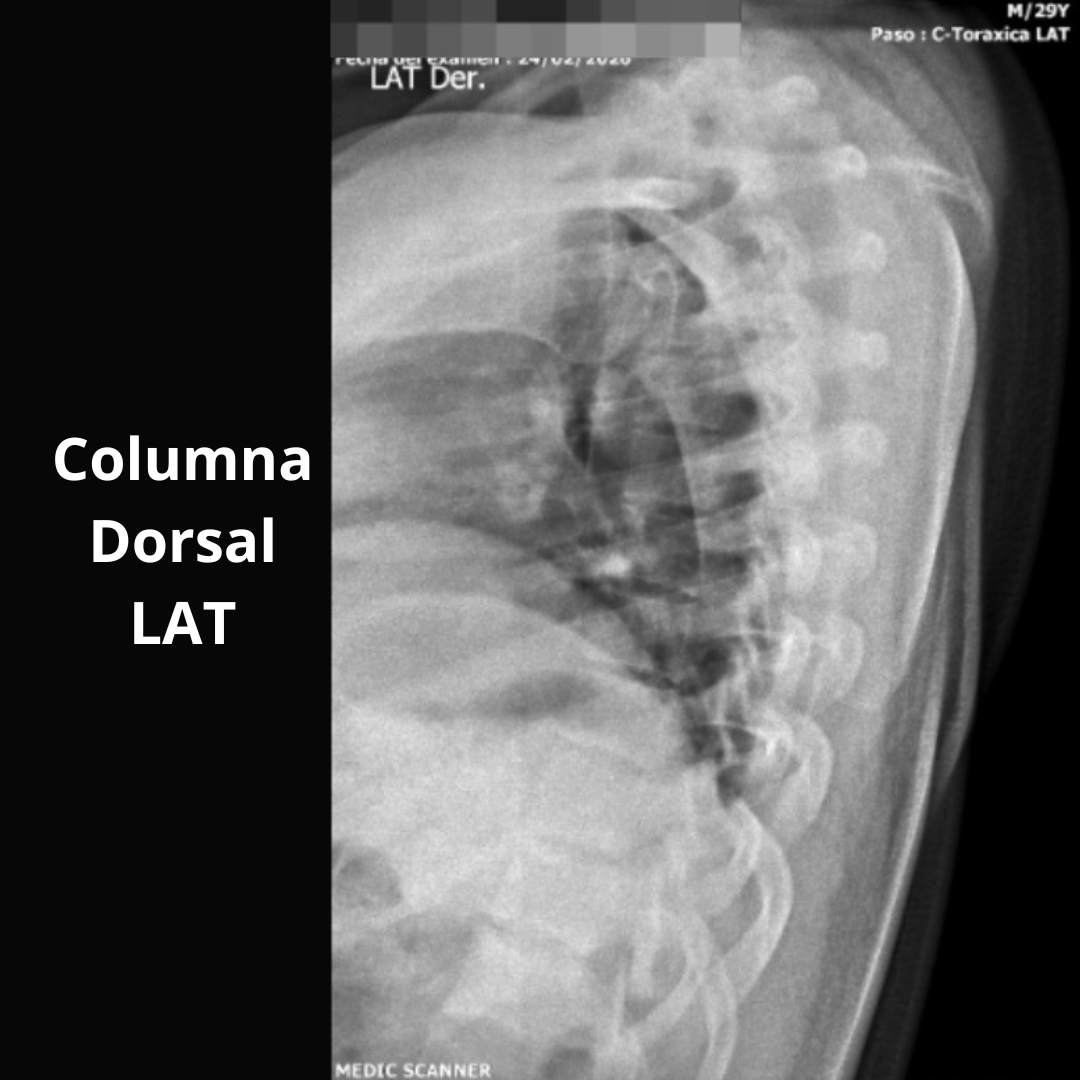

- Columna Dorsal O AP O LAT O OBL